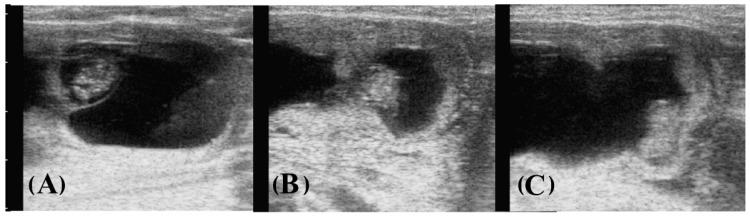

This study provides new unique information on bovine twin pairs during the late embryonic period (28-34 days of pregnancy) in relation to (1) a predictive ultrasound measurement that was differential for sexing heterosexual twins; (2) intrauterine embryonic growth patterns in twin pairs; and (3) a higher vulnerability of female embryos compared to males following an induced embryo reduction in heterosexual twins. The study population comprised 92 dairy cows carrying bilateral twins. A length difference between co-twins equal to or greater than 25% in around 50% of pregnancies served to determine the sex of embryos with 100% accuracy in heterosexual twins, which was assessed four weeks later on the remaining fetus after twin reduction. The apparent rates of growth of twin pairs and of individual male and female embryos from day 28 to 34 of gestation were similar to established growth pattern standards for singletons. Mean embryo sizes in relation to gestational age were smaller by some 5 days' growth equivalent in twins compared to singletons. After the reduction in the female embryo in heterosexual twins, the risk of male embryo loss was null. This new information allowed for sex selection at the time of twin reduction.

本研究提供了关于妊娠后期(妊娠28 - 34天)牛双胞胎的全新独特信息,涉及以下方面:(1)一种用于区分异性双胞胎性别的预测性超声测量方法;(2)双胞胎对中子宫内胚胎的生长模式;(3)在异性双胞胎中进行人工胚胎减灭后,雌性胚胎相较于雄性胚胎具有更高的脆弱性。研究群体包括92头怀有双侧双胞胎的奶牛。在约50%的妊娠中,双胞胎之间的长度差异等于或大于25%,可用于以100%的准确率确定异性双胞胎胚胎的性别,在减胎四周后对剩余胎儿进行评估。从妊娠第28天到第34天,双胞胎对以及单个雄性和雌性胚胎的表观生长速率与已确立的单胎生长模式标准相似。与单胎相比,双胞胎中与胎龄相关的平均胚胎大小约小5天的生长当量。在异性双胞胎中减灭雌性胚胎后,雄性胚胎丢失的风险为零。这些新信息使得在减胎时能够进行性别选择。